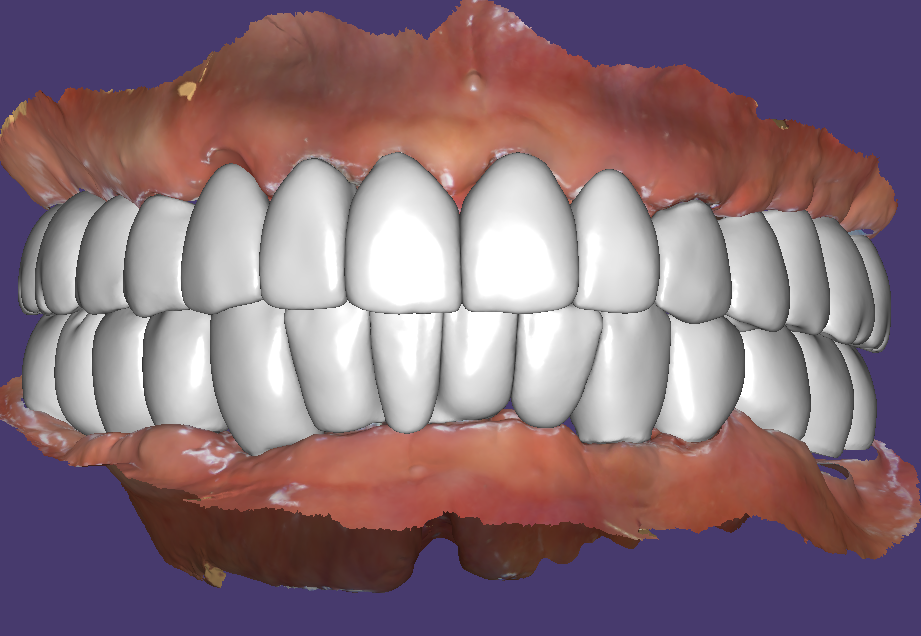

브릿지타입의 지르코니아 최종보철 세팅과정

이렇게 충분한 개수의 임플란트로 치료하면 원래 치아모양과 유사한 형태의 치아디자인이 가능합니다.

전체임플란트 치료완료

치료전 상태가 안 좋았지만 이제는 정상적인 오버젯을 가진 아름다운 모양으로 치료가 완료되었습니다. 치열의 구조가 좋으면 심미적으로 우수한 것은 당연하고 기능적으로도 훨씬 좋고 이후 장기간 사용시 문제가능성도 줄어들게 됩니다.